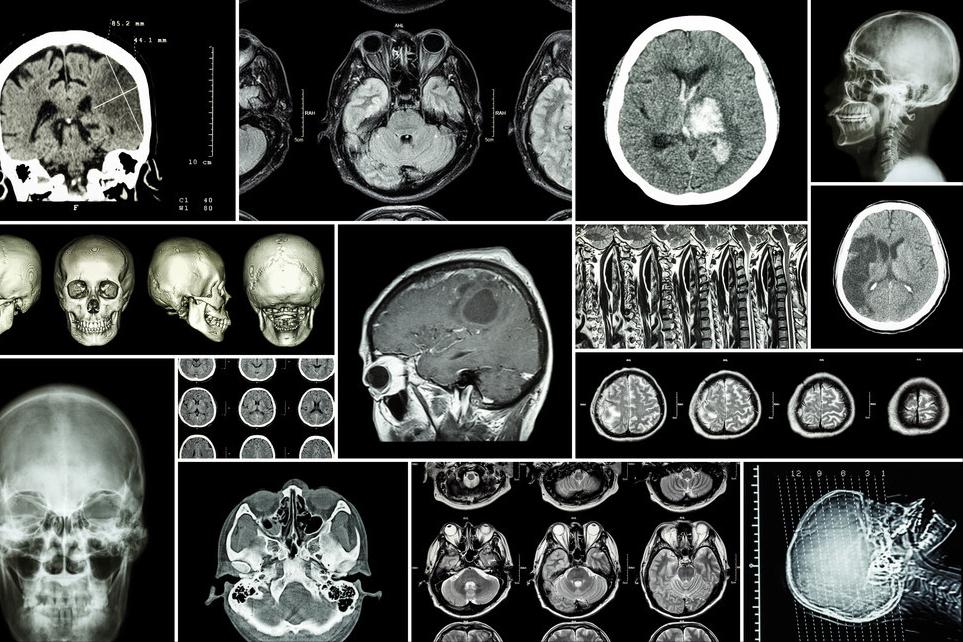

短暂性脑缺血发作,是急性缺血性脑血管病之一,是缺血性卒中的高危信号,一旦发生,必须立即送往医院治疗,因为“时间就是大脑”。

短暂性脑缺血发作是指在一定时间之内缺血的症状发作后,同时又很快缓解,以前把时间定在24小时,现在定义为在一小时内,缺血的症状很快恢复。症状包括很多,一种情况是常见脑梗死的症状,表现为一侧肢体活动不灵活或者头痛、头晕、视物旋转,可能会出现某肢体突然偏瘫,过半小时自己恢复,或者是下肢不能走路,过一段时间自己恢复。

另一种情况就是短暂性脑缺血发作只是后循环缺血,这种的有可能会行走时突然下肢无力,发生跌倒,没有明显的肢体活动障碍,但只是跌倒发作,也是短暂性脑缺血发作的症状。短暂性脑缺血发作的症状和脑梗死的症状一致,不同在于短暂性脑缺血发作的症状在一小时内可以很快恢复。